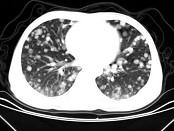

问题 男,42岁,肝区痛1月余,最近2周咯血丝痰,胸部CT如图,最可能的诊断为 ( )

选项 A.葡萄球菌肺炎 B.过敏性肺炎 C.结节病 D.肺转移瘤 E.韦格肉芽肿

答案 D